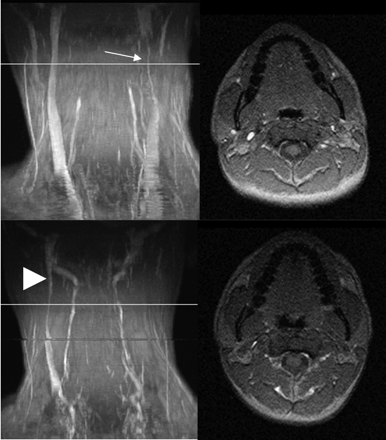

MIP (left column) and axial source images at the level of C2 in supine (top row) and sitting positions (bottom row) in a healthy volunteer. In the supine position, there is a high-grade stricture of the left jugular vein (arrow). The EJV and VP are visible. In the sitting position, only the right IJV is visible (arrowhead). The NV are prominent, and the VP can be identified.

Table 2 shows the delineation of the IJV and the presence or absence of strictures. A so-called “normal” CVBO pattern without any significant narrowing of 1 or 2 of the IJVs in the supine position was only seen in 7 volunteers (Figs 1 and 2). The other 8 volunteers had significant strictures of at least 1 IJV in the superior portion (Figs 3 and 4). In 3 of these 8 volunteers with a significant stenosis of the IJV in the supine position, the IJV was only delineated in the sitting position on both sides and in 2 volunteers on 1 side. It was, however narrowed compared with the findings in the supine position. The narrowing was homogeneous, and no stricture in the course of the IJV was observed. In the remaining 3 volunteers with a significant stenosis of the IJV in the supine position, the IJV was not delineated in the sitting position.